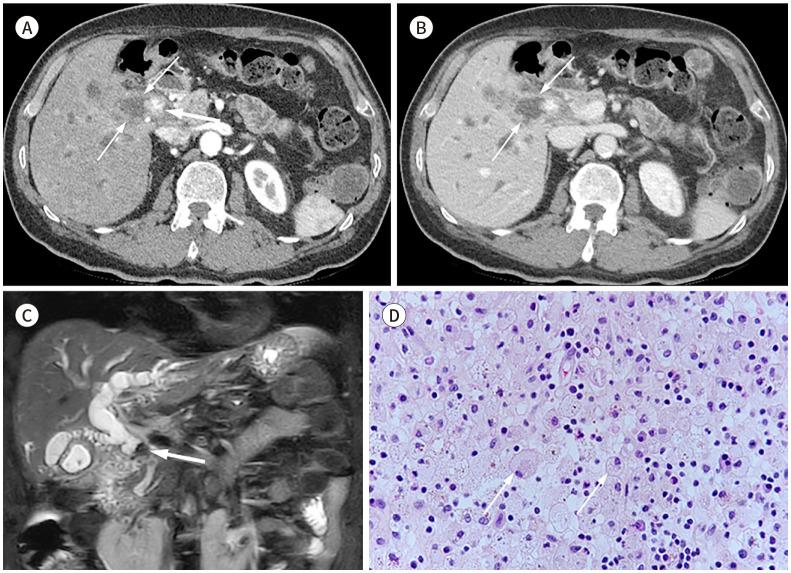

Xanthogranulomatous (XG) inflammatory disease is a rare benign disease involving various organs, including the gallbladder, bile duct, pancreas, spleen, stomach, small bowel, colon, appendix, kidney, adrenal gland, urachus, urinary bladder, retroperitoneum, and female genital organs. The imaging features of XG inflammatory disease are nonspecific, usually presenting as a heterogeneous solid or cystic mass. The disease may also extend to adjacent structures. Due to its aggressive nature, it is occasionally misdiagnosed as a malignant neoplasm. Herein, we review the radiological features and clinical manifestations of XG inflammatory diseases in various organs of the abdomen and pelvis.

黄色肉芽肿性(XG)炎性疾病是一种罕见的良性疾病,可累及包括胆囊、胆管、胰腺、脾脏、胃、小肠、结肠、阑尾、肾脏、肾上腺、脐尿管、膀胱、腹膜后间隙及女性生殖器官在内的多个器官。XG炎性疾病的影像学特征不具有特异性,通常表现为不均匀的实性或囊性肿块。该疾病也可能蔓延至相邻结构。因其具有侵袭性,偶尔会被误诊为恶性肿瘤。在此,我们回顾腹部和盆腔各器官XG炎性疾病的放射学特征及临床表现。